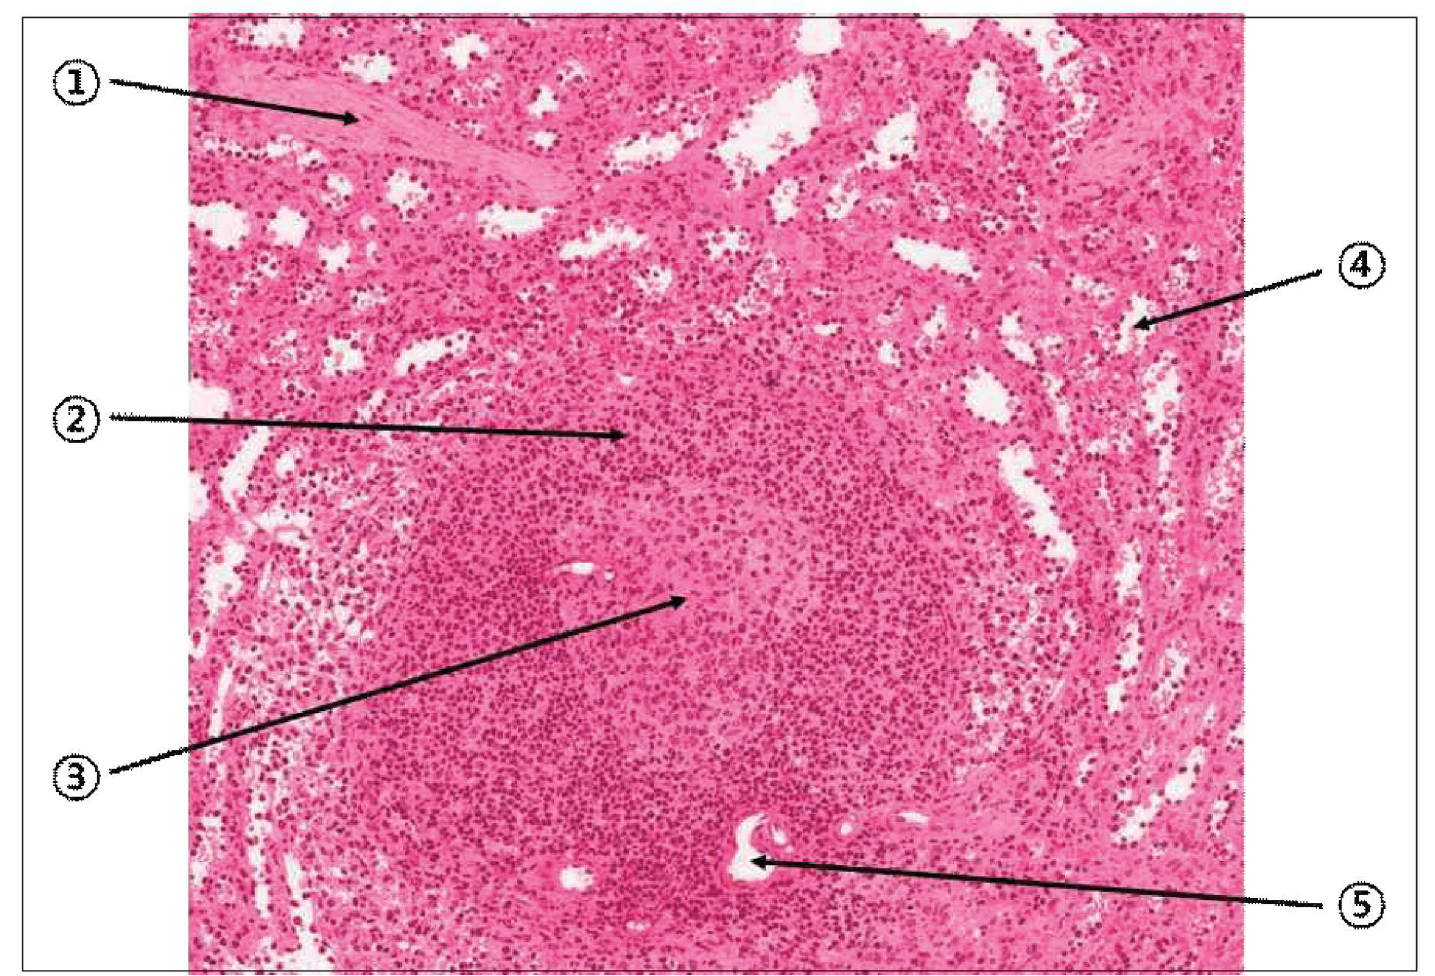

가슴샘

- reticular cell과 그것이 회오리치는 thymic corpuscle(hassall's corpuscle)을 가진다.

- cortex와 medulla로 구성된 lobule은 septum로 구분되고, 전체를 capsule이 감싼다.

- T cell은 cortex에서 medulla 방향으로 이동한다. 이때 epithelial reticular cell과 desmosome이 검문을 수행한다.